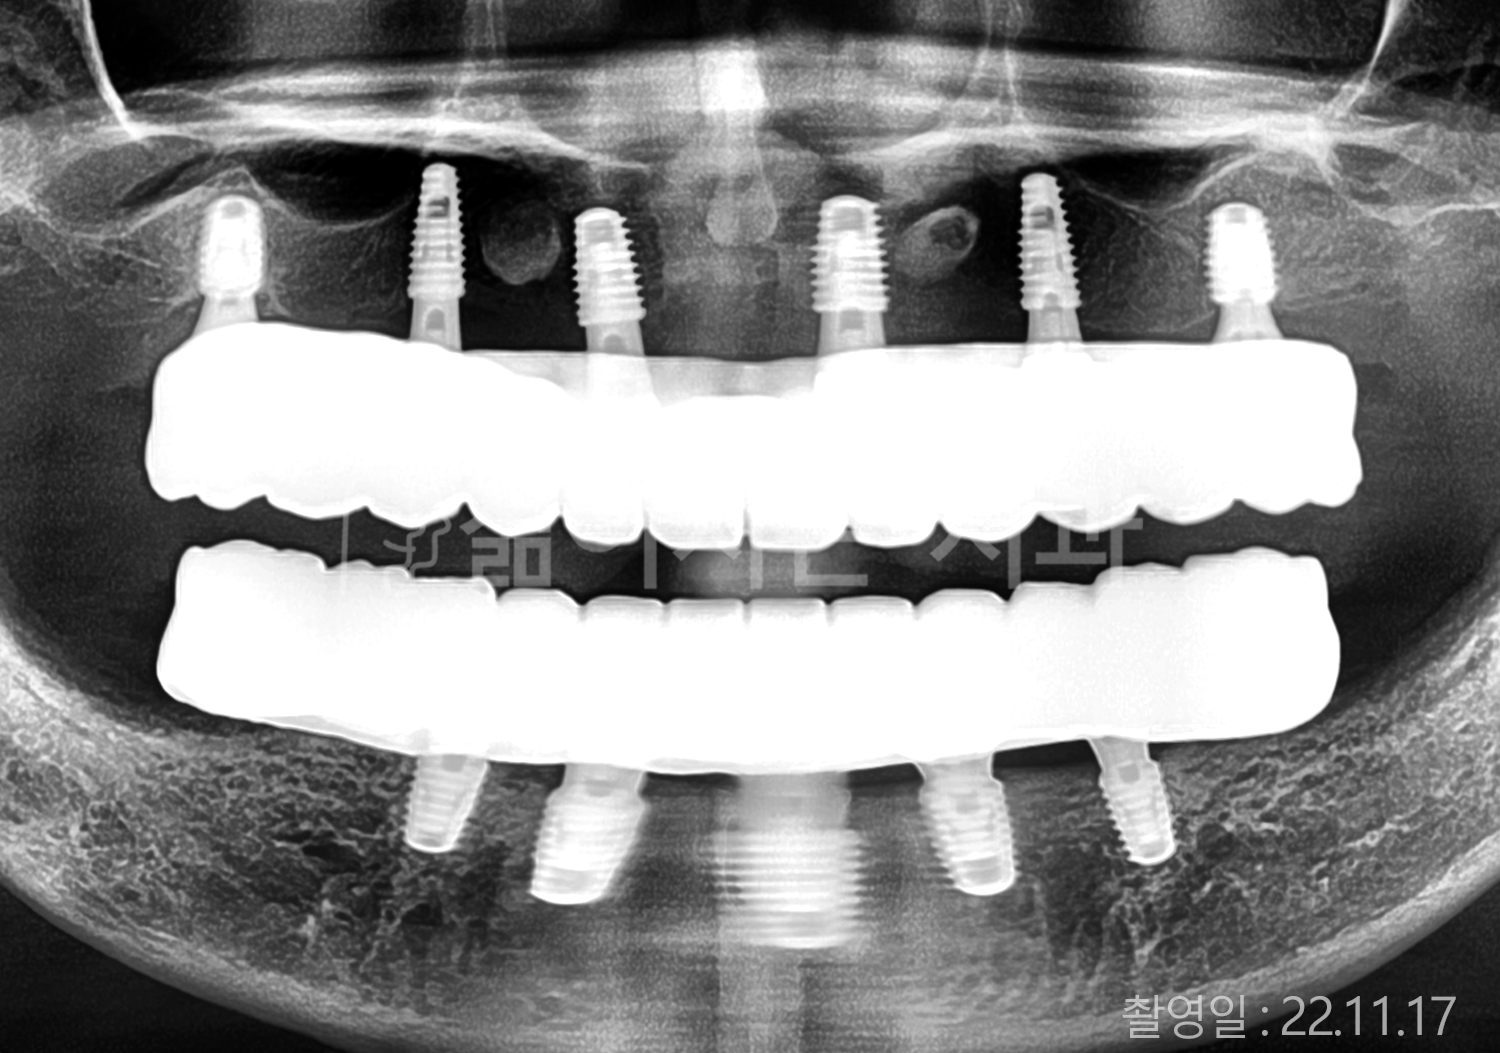

• 80대 전체치아 10개 이상 임플란트

• 60대 고혈압, 당뇨, 고지혈증 전체치아 10개 이상 임플란트

• 60대 전체치아 10개 이상 임플란트

• 60대 고혈압, 고지혈증 전체치아 10개 이상 임플란트

• 50대 고혈압, 당뇨, 고지혈증 전체치아 10개 이상 임플란트

• 70대 골다골증, 파킨스병 전체치아 10개 이상 임플란트

• 40대 전체치아 10개 이상 임플란트

• 60대 골다골증 전체치아 10개 이상 임플란트

• 40대 고혈압 전체치아 10개 이상 임플란트

• 50대 전체치아 10개 이상 임플란트

• 70대 전체치아 10개 이상 임플란트